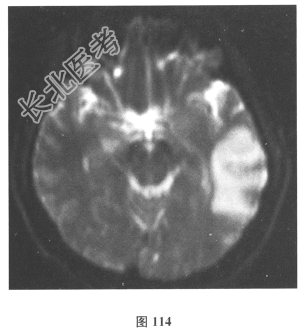

脑脊液检查:常规、生化均正常,CSF-病毒TORCH(-),抗Hu、Yo、Ri均阴性,OB、MBP正常。血清抗Hu、Yo、Ri均阴性。颅脑MRI显示左颞枕、右顶枕多发长T₁、长T₂信号,Flair高信号,病变累及皮质及皮质下白质,病灶无强化,见图108~图114。)根据颅脑MRI,需要鉴别的疾病应是